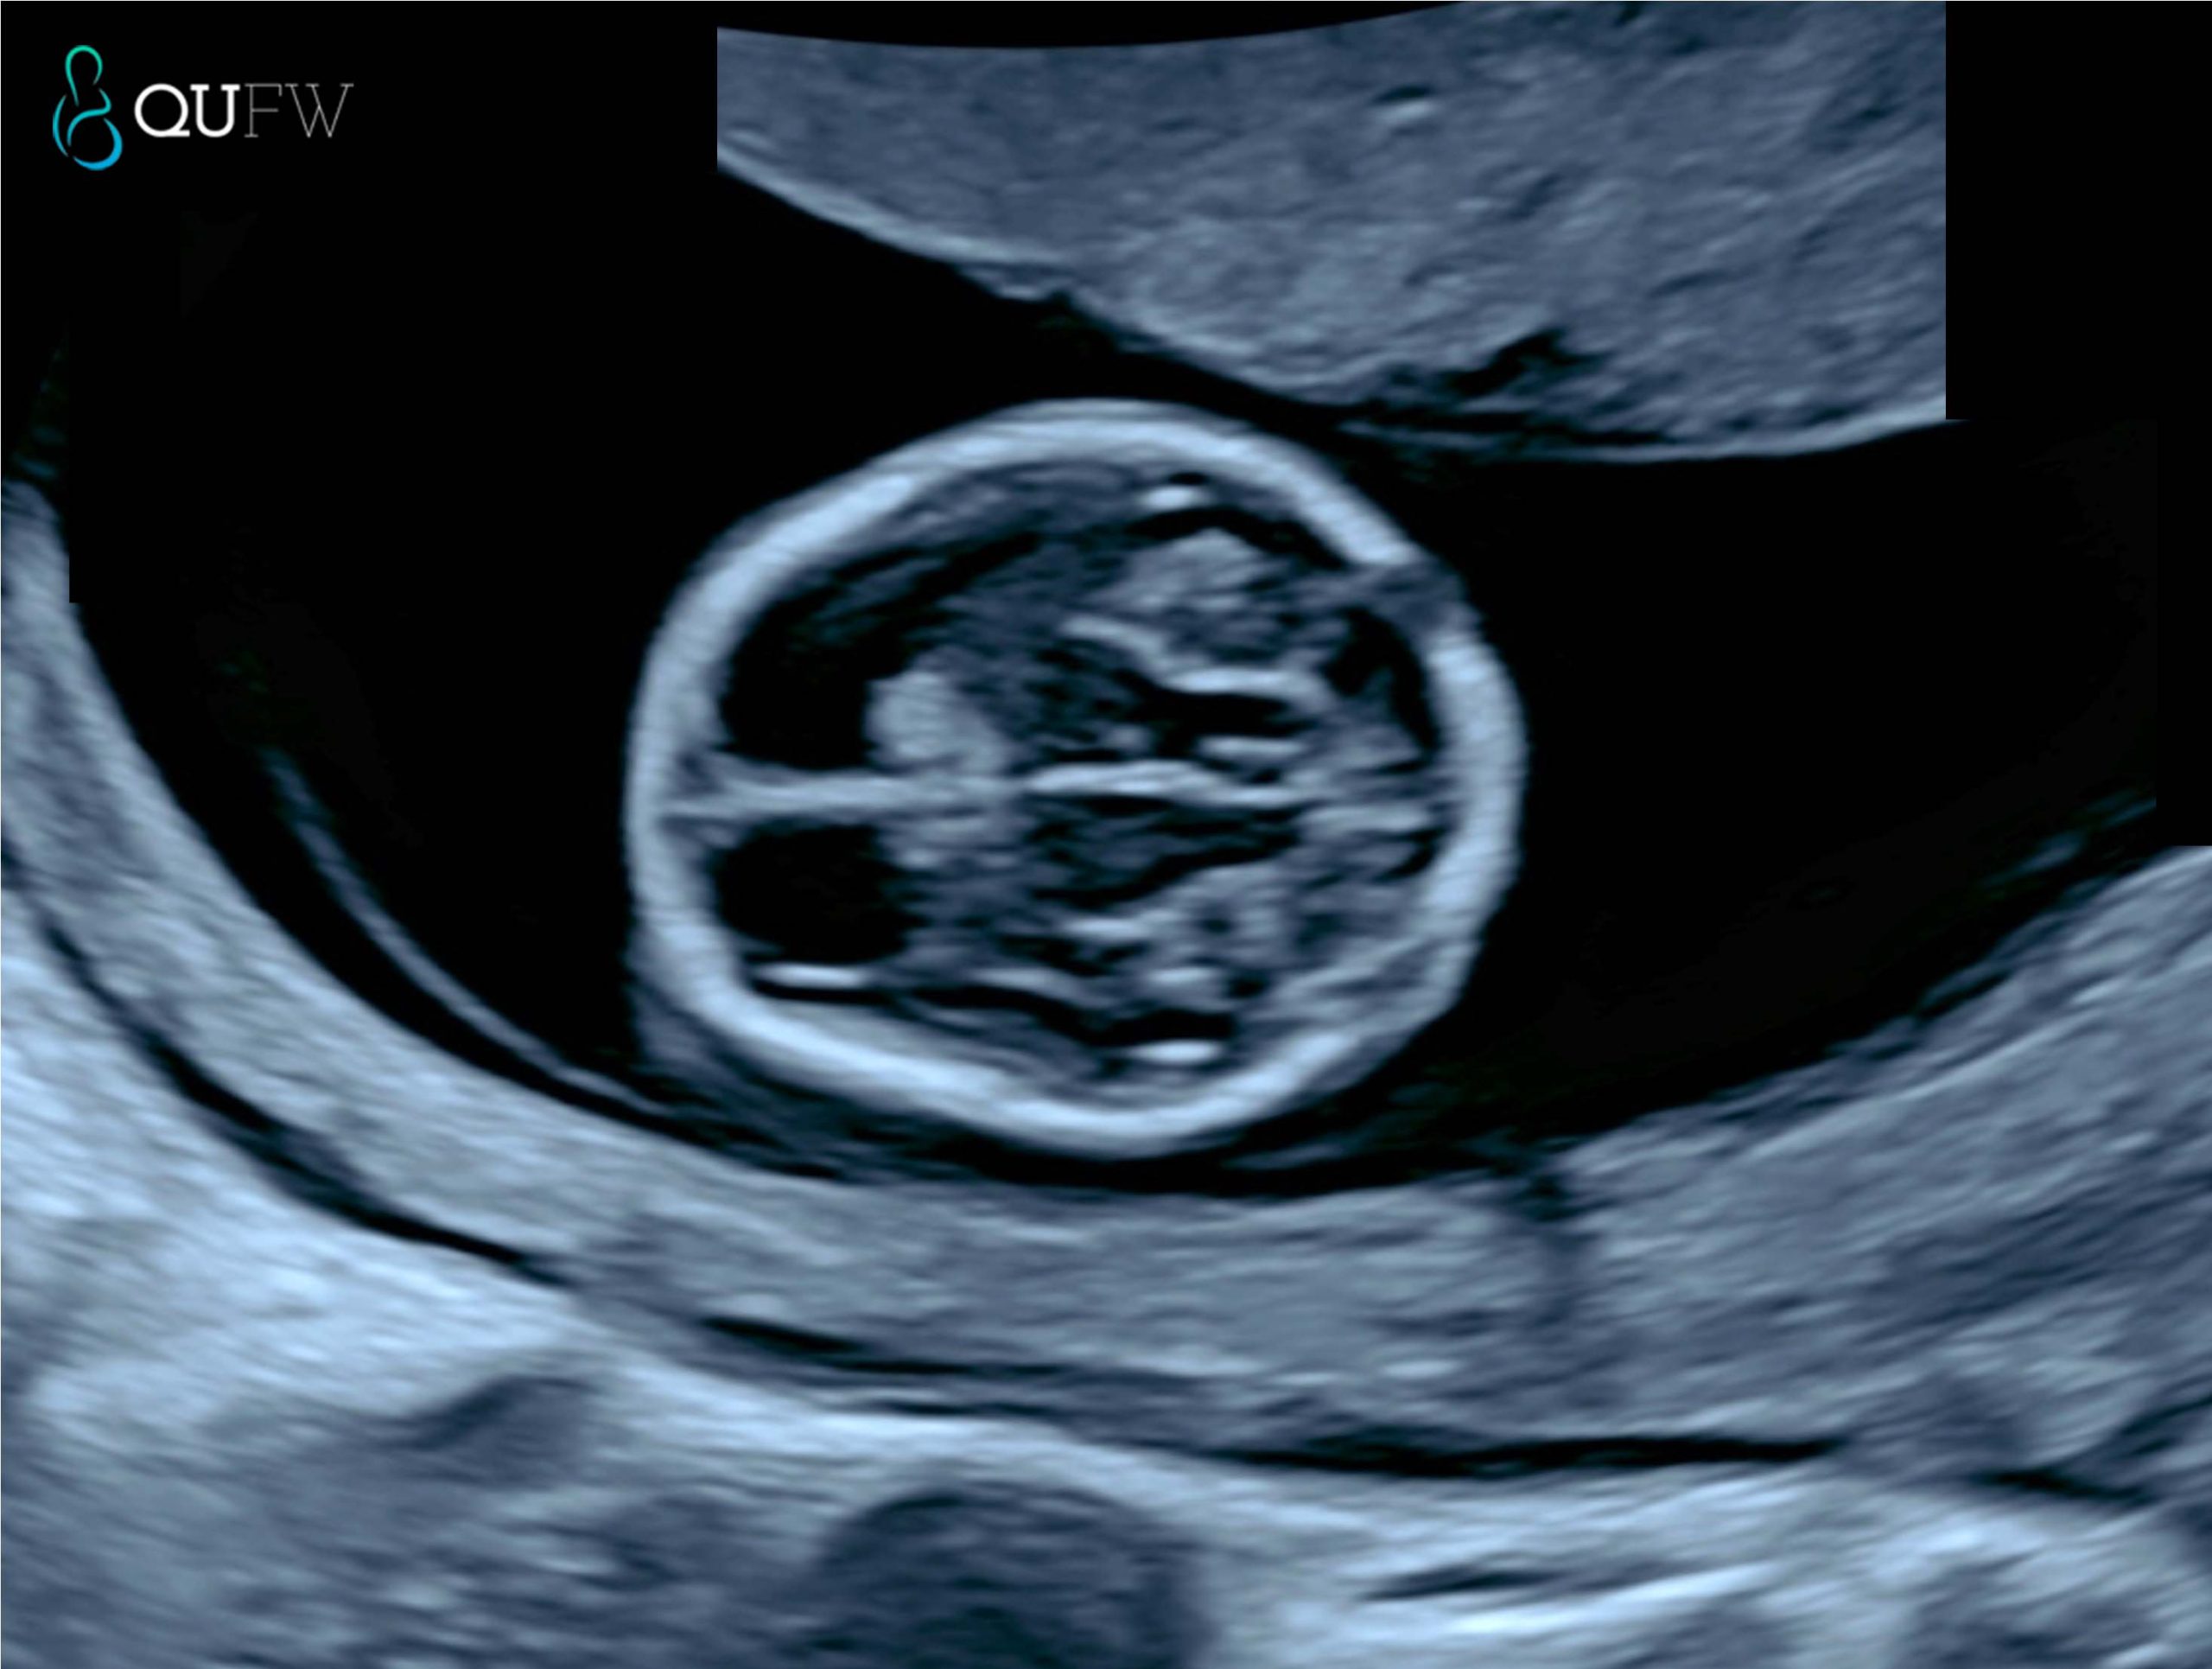

Early structural assessment of the fetal brain